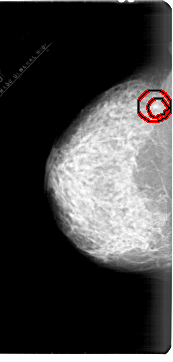

A_1878_1.LEFT_CC

LEFT_CC LINES 6871 PIXELS_PER_LINE 3286 BITS_PER_PIXEL 12 RESOLUTION 43.5 OVERLAY

FILE: A_1878_1.LEFT_CC.OVERLAY

TOTAL_ABNORMALITIES 1

ABNORMALITY 1

LESION_TYPE MASS SHAPE IRREGULAR MARGINS SPICULATED

ASSESSMENT 4

SUBTLETY 1

PATHOLOGY BENIGN

TOTAL_OUTLINES 2

BOUNDARY

CORE